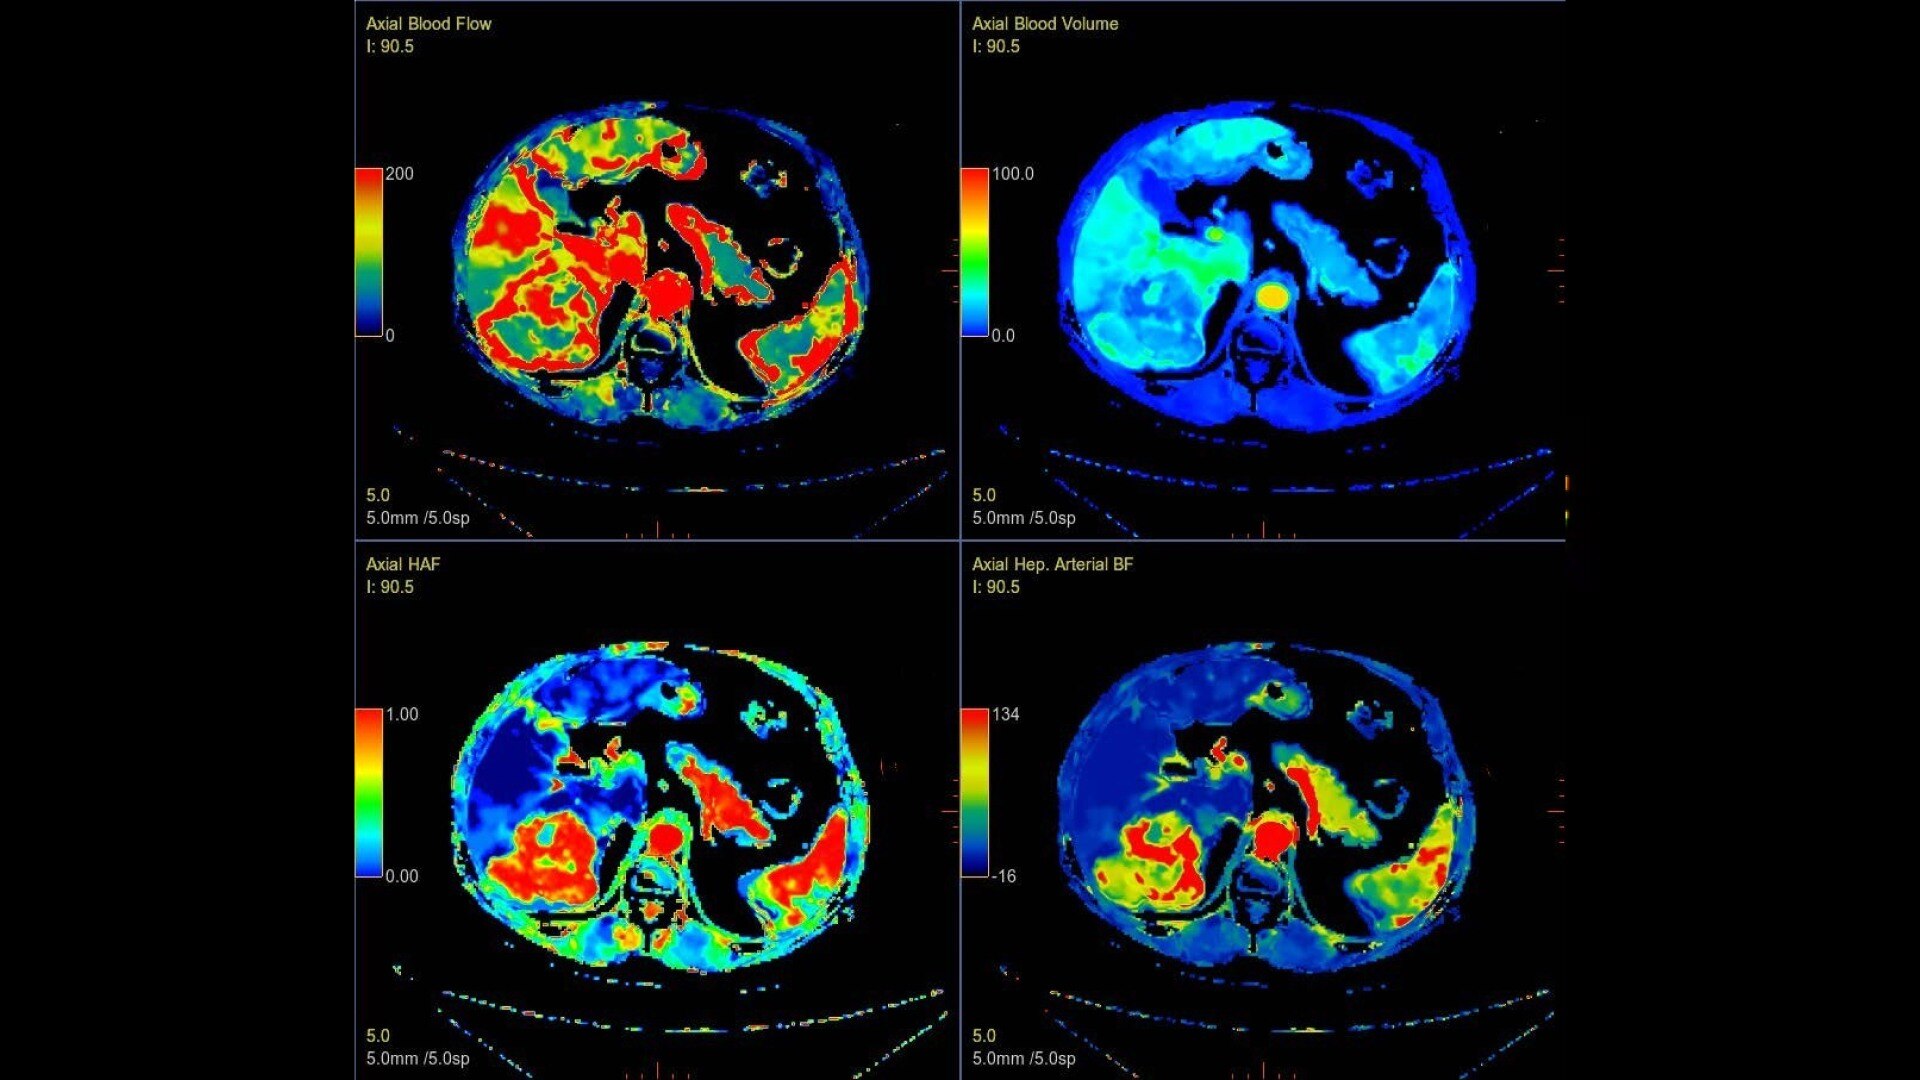

Body perfusion

Optimized protocols for kidney, soft tissue, liver perfusion and other body tumors

CT Body Tumor Protocol

• Automatically produces functional maps once the user selects an artery using a simple and intuitive workflow

• Leverages most of the advanced algorithm settings that are part of the Brain Stroke protocol

• Optimized protocols for pancreas, prostate, kidney, soft tissue, spleen, bone and liver perfusion

• CT Non-Rigid Registration: Fully automated protocols used for dynamic body acquisitions to register data for use in perfusion analysis